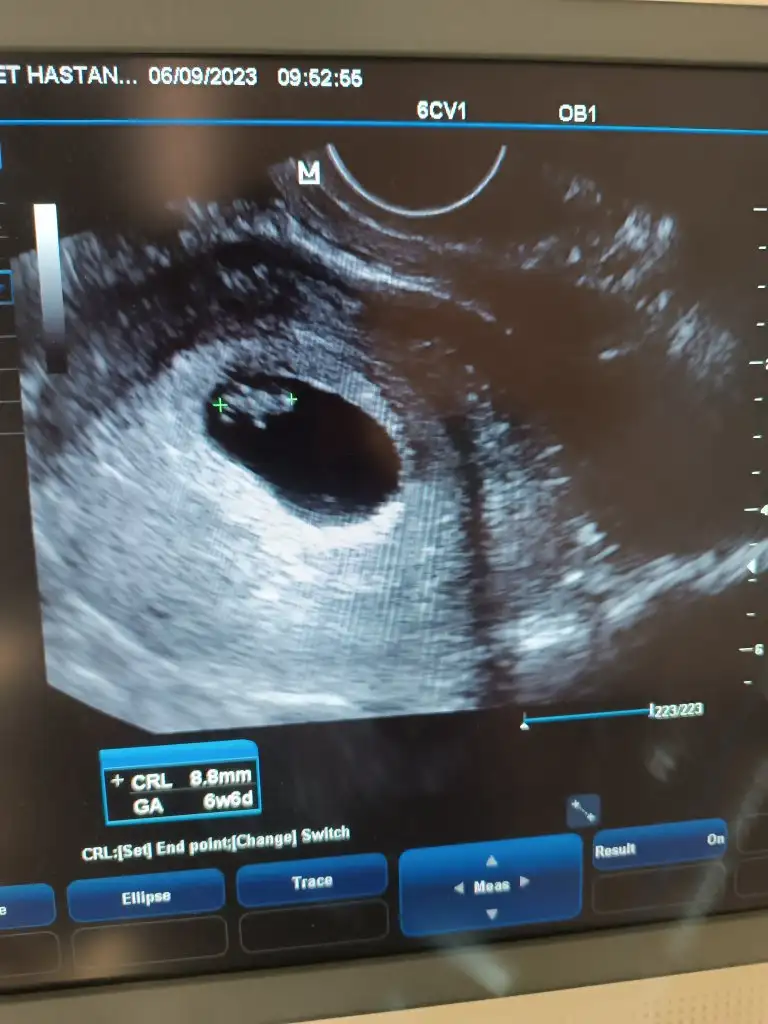

7+1 tahmin yapabilir misiniz Hülya hanımCanîm kıza çok benziyo hayırlısı olsun inşallah senne hissediyosun

Burada bebeğin konumununa göre yorum yapmışlar ama ramzi teorisi plasentanın konumuna göre bilgi veriyor diye biliyorum ben. Plasentanın da nerede olduğunu göremedim 2 gündür:)Konu biteli yıllar olmuş ama belki yorum gelir 7+4 karındanEki Görüntüle 3454856